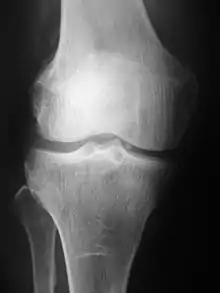

التصوير الطبقي المحوري (الأشعة السينية)

مقالة مفصلة: الأشعة السينية

تنتج الأشعة الشعاعية (التي كانت تسمى في الأصل رونتغن الشعاعي؛ التي سميت على اسم مكتشف الأشعة السينية فيلهلم كونراد رونتغن) عن طريق نقل الأشعة السينية عبر المريض. من المتوقع أن يتم تصوير الأشعة السينية عبر الجسم على كاشف. يتم تكوين صورة بناءً على أي أشعة تمر عبرها (ويتم اكتشافها) مقابل تلك التي يتم امتصاصها أو تشتيتها في المريض (وبالتالي لا يتم اكتشافها). اكتشف رونتغن الأشعة السينية في 8 نوفمبر 1895، وحصل على أول جائزة نوبل في الفيزياء لاكتشافها في عام 1901.

في التصوير الشعاعي للشاشة ، يولد أنبوب الأشعة السينية شعاعًا من الأشعة السينية التي تستهدف المريض. يتم ترشيح الأشعة السينية التي تمر عبر المريض من خلال جهاز يسمى الشبكة أو مرشح الأشعة السينية؛ للحد من التشتت ، وإصابة فيلم غير متطور ، والذي يتم تثبيته بإحكام إلى شاشة من الفوسفور التي ينبعث منها ضوء في كاسيت خفيف ثم يتم تطوير الفيلم كيميائيا وتظهر صورة على الفيلم. يتم استبدال التصوير الشعاعي للسينما بالأشعة الفسفورية ولكن في الآونة الأخيرة بواسطة التصوير الشعاعي الرقمي (DR) والتصوير EOS. في النظامين الأحدث تعمل مستشعرات الأشعة السينية التي تقوم بتحويل الإشارات المتولدة إلى معلومات رقمية، والتي يتم نقلها وتحويلها إلى صورة معروضة على شاشة الكمبيوتر. في التصوير الشعاعي الرقمي تشكل المستشعرات صفيحة(لوحة)، ولكن في نظام EOS؛ وهو عبارة عن نظام مسح للفتحة، يقوم مستشعر خطي بفحص المريض رأسياً.

كان التصوير الشعاعي العادي (الأشعة السينية x-ray) هو أسلوب التصوير الوحيد المتاح خلال أول 50 عامًا من الأشعة. نظرًا لتوفرها وسرعتها وتكاليفها المنخفضة مقارنة بالطرائق الأخرى، فإن التصوير الشعاعي غالبًا ما يكون اختبار الخط الأول للاختيار في التشخيص الإشعاعي. أيضًا على الرغم من الكم الهائل من البيانات في التصوير المقطعي ، وفحوصات الرنين المغناطيسي وغيرها من التصوير الرقمي ، هناك العديد من الكيانات المرضية التي يتم فيها الحصول على التشخيص الكلاسيكي عن طريق صور الأشعة العادية. وتشمل الأمثلة أنواع مختلفة من: التهاب المفاصل والالتهاب الرئوي، وأورام العظام (وخاصة أورام العظام الحميدة)، والكسور، والشذوذات الهيكلية الخلقية.. إلخ.